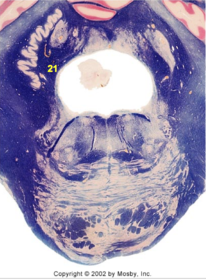

| CN IX | |

| Inferior cerebellar peduncle | |

| Inferior olivary complex | |

| Dorsal cochlear nucleus | |

| Inferior vestibular nucleus | |

| Medial vestibular nucleus | |

| Spinal nucleus of V | |

| Spinal tract of V | |

| Medullary pyramids | |

| Solitary nucleus | |

| ALS | |

| Medial lemniscus | |

| Medial longitudinal fasciculus | |

| Ventral cochlear nucleus | |

| Anterior spinocerebellar tract | |

| Central tegmental tract | |

| Olivary internal arcuate fibers | |

| Solitary tract | |

| Abducens root fibers | |